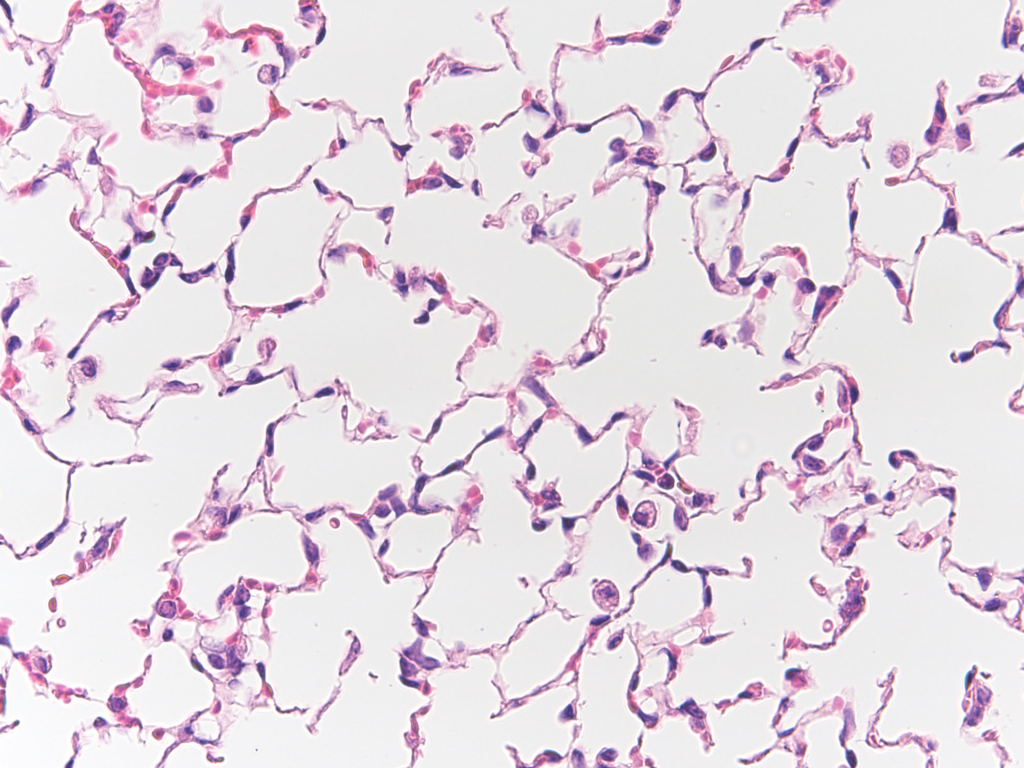

Emphysema progression in chronic obstructive pulmonary disease (COPD) presents a notable challenge due to its significant variability among individuals and the current lack of reliable prognostic markers. Given the limited therapeutic options available for emphysema, there is a critical need for early detection and intervention strategies. Identifying individuals at risk of rapid progression is essential to effectively halt or slow the disease’s advancement. This study introduces an innovative approach employing a localized foundational model of density evolution to pinpoint local radiographic embeddings indicative of emphysema progression. Central to our methodology is the Local Emphysema Progression (LEP) score, a novel metric derived from our model that aggregates localized lung tissue activations into a comprehensive, subject-level risk assessment tool. The model’s performance was tested on 3728 COPDGene participants, comparing baseline to 5-year, and 1421 scans taken from the 5-year to 10-year interval period. Additionally, our findings were replicated in 1058 ECLIPSE participants. The model effectively identifies lung regions with emphysema progression, achieving an AUC of 0.88. The LEP risk score shows good correlation with the change in the percentage of low attenuation areas below −950 Hounsfield Units (Δ%LAA-950), with correlation values of 0.50 in the COPDGene cohort and 0.40 in the ECLIPSE cohort among subjects with emphysema progression (Δ%LAA-950 > 0). Furthermore, LEP risk score associates with mortality and several COPD outcomes, underscoring its potential as a valuable tool in clinical prognosis and management of emphysema progression in COPD patients.